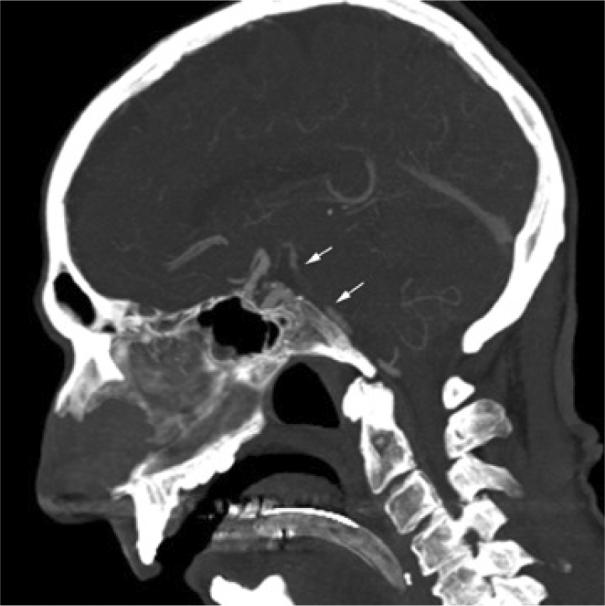

We present a case of an elderly male with sudden onset of a posterior circulation stroke that rapidly progressed to a deteriorating level of consciousness. Despite a dismal prognosis due to his age, the cause of his stroke, and his rapid clinical deterioration, he had an exceptional outcome. We attribute his favorable outcome to a number of factors including his good premorbid health, his timely presentation for definitive diagnosis and treatment, and rapid re-establishment and maintenance of flow in his occluded basilar artery using several endovascular techniques. The case report is exemplary of what may be achieved in elderly patients with acute posterior circulation stroke in contradistinction to what has been previously thought to be a universally fatal disease.

我们报告一例老年男性患者,其突发后循环卒中,意识水平迅速恶化。尽管由于其年龄、卒中病因及临床快速恶化,预后不佳,但他却取得了超乎寻常的结果。我们将他良好的预后归因于多种因素,包括病前健康状况良好、及时就诊以明确诊断和治疗,以及使用多种血管内技术迅速重建并维持其闭塞基底动脉的血流。该病例报告表明,与之前认为普遍致命的疾病相反,老年急性后循环卒中患者可能取得较好的治疗效果。